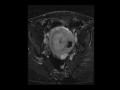

Intracavitary fibroid

MR images demonstrate a large intracavitary fibroid that is T2 hypointense and enhances similar to the background uterus.